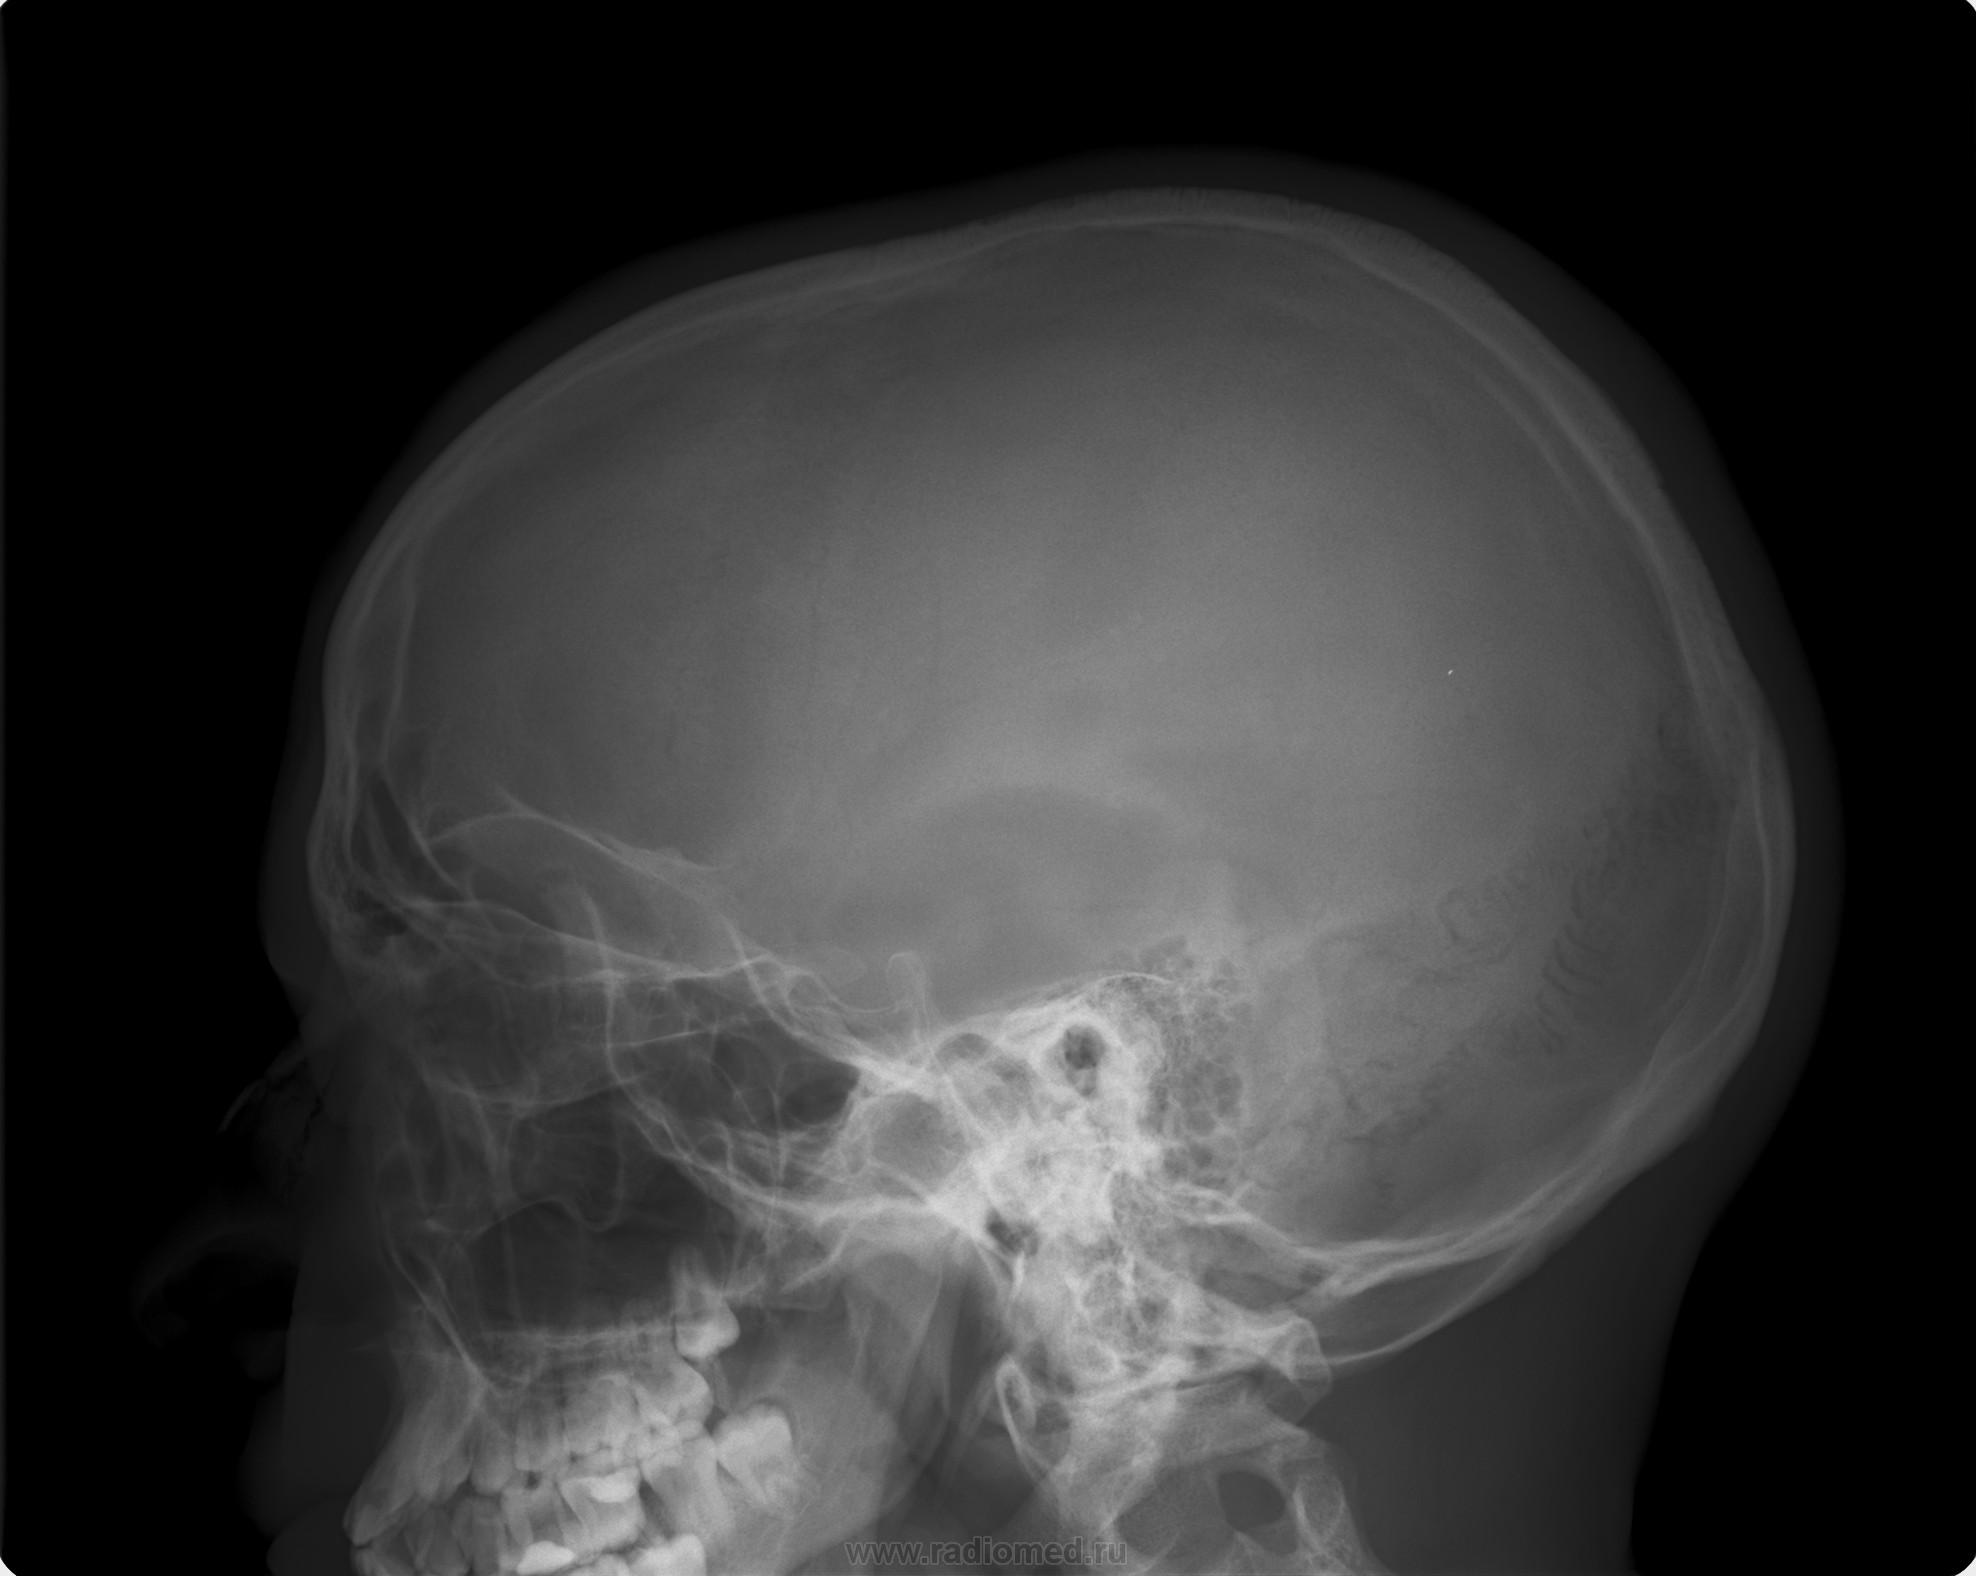

Рентгенография черепа и позвоночника: изображение и диагностика